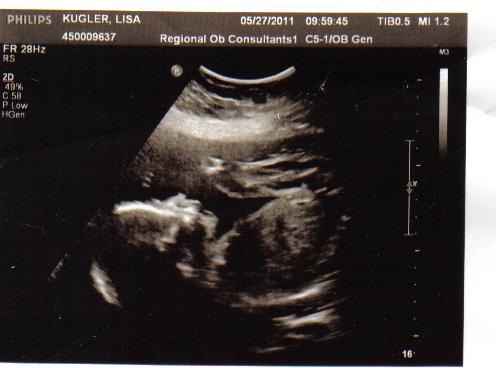

You know its a good appointment when your doctor gives you a High Five in the middle of the ultrasound. No hydrocephalus was seen! So that is awesome news which we hope continues. Her legs are busy. (In fact those are her legs folded up by her face in the image). So that's awesome too! We still don't have any more information about the placement of her lesion than we had before, but as far as can be seen now, she has no club feet or scoliosis-both of which frequently accompany spina bifida. Her chiari is still there, but her head measurements are only two weeks behind her body now, when it was 3 weeks behind last month...so I suppose that's improvement too. (Again her head isn't REALLY smaller, it just measures that way because of the change in shape...but no worries...her head will look normal at birth. I won't actually be shaped like a lemon. lol) She is small overall though, weighing in at 1lb 5oz and measuring 22 weeks instead of 24 weeks, but she's still well in normal range- she's just petite. ( Ha! with a 5'10"inch mom and a 6' 5" dad, that'll probably be the LAST time anybody calls her petite!) I also figure I should probably lay off the caffeine and try to eat more to help her fatten up and grow! :)